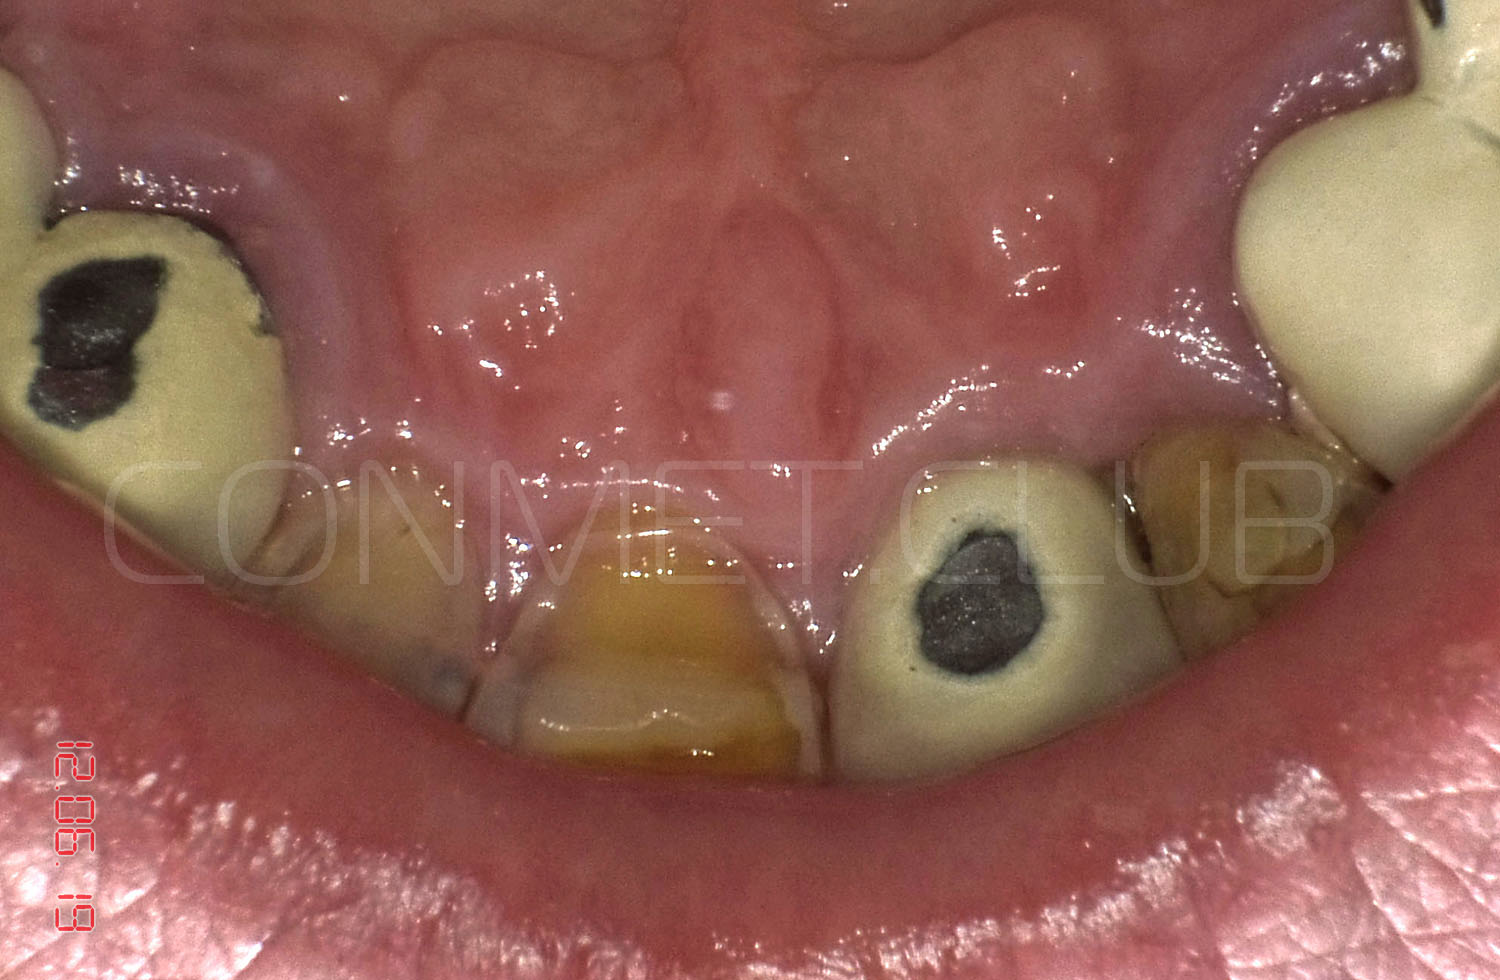

Операция немедленной имплантации была произведена 27.02.2004 года непосредственно после экстракции зуба 21 из-за невозможности дальнейшего лечения данного зуба (две вертикальные трещины корня).

Вид на корень и трещины за три дня до экстракции и немедленной имплантации.

Вид на лунку удаленного зуба. Щипцы при удалении не использовались, только кюретажная ложка СМ 2/4 и прямой элеватор.